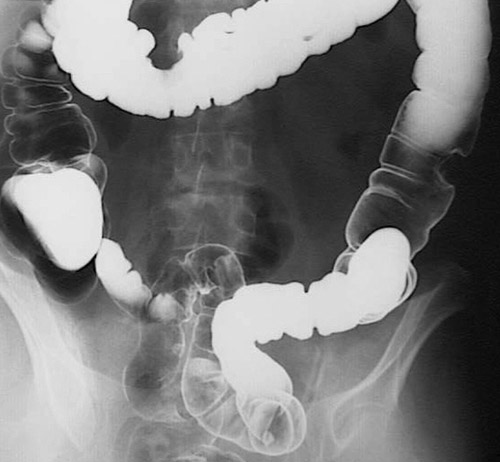

Two sessile masses, one in the transverse colon and one in the descending colon are seen in this barium enema. These masses are larger than 2 cm and, statistically, are likely to be adenocarcinomas. Indeed, histologically, they were malignant.